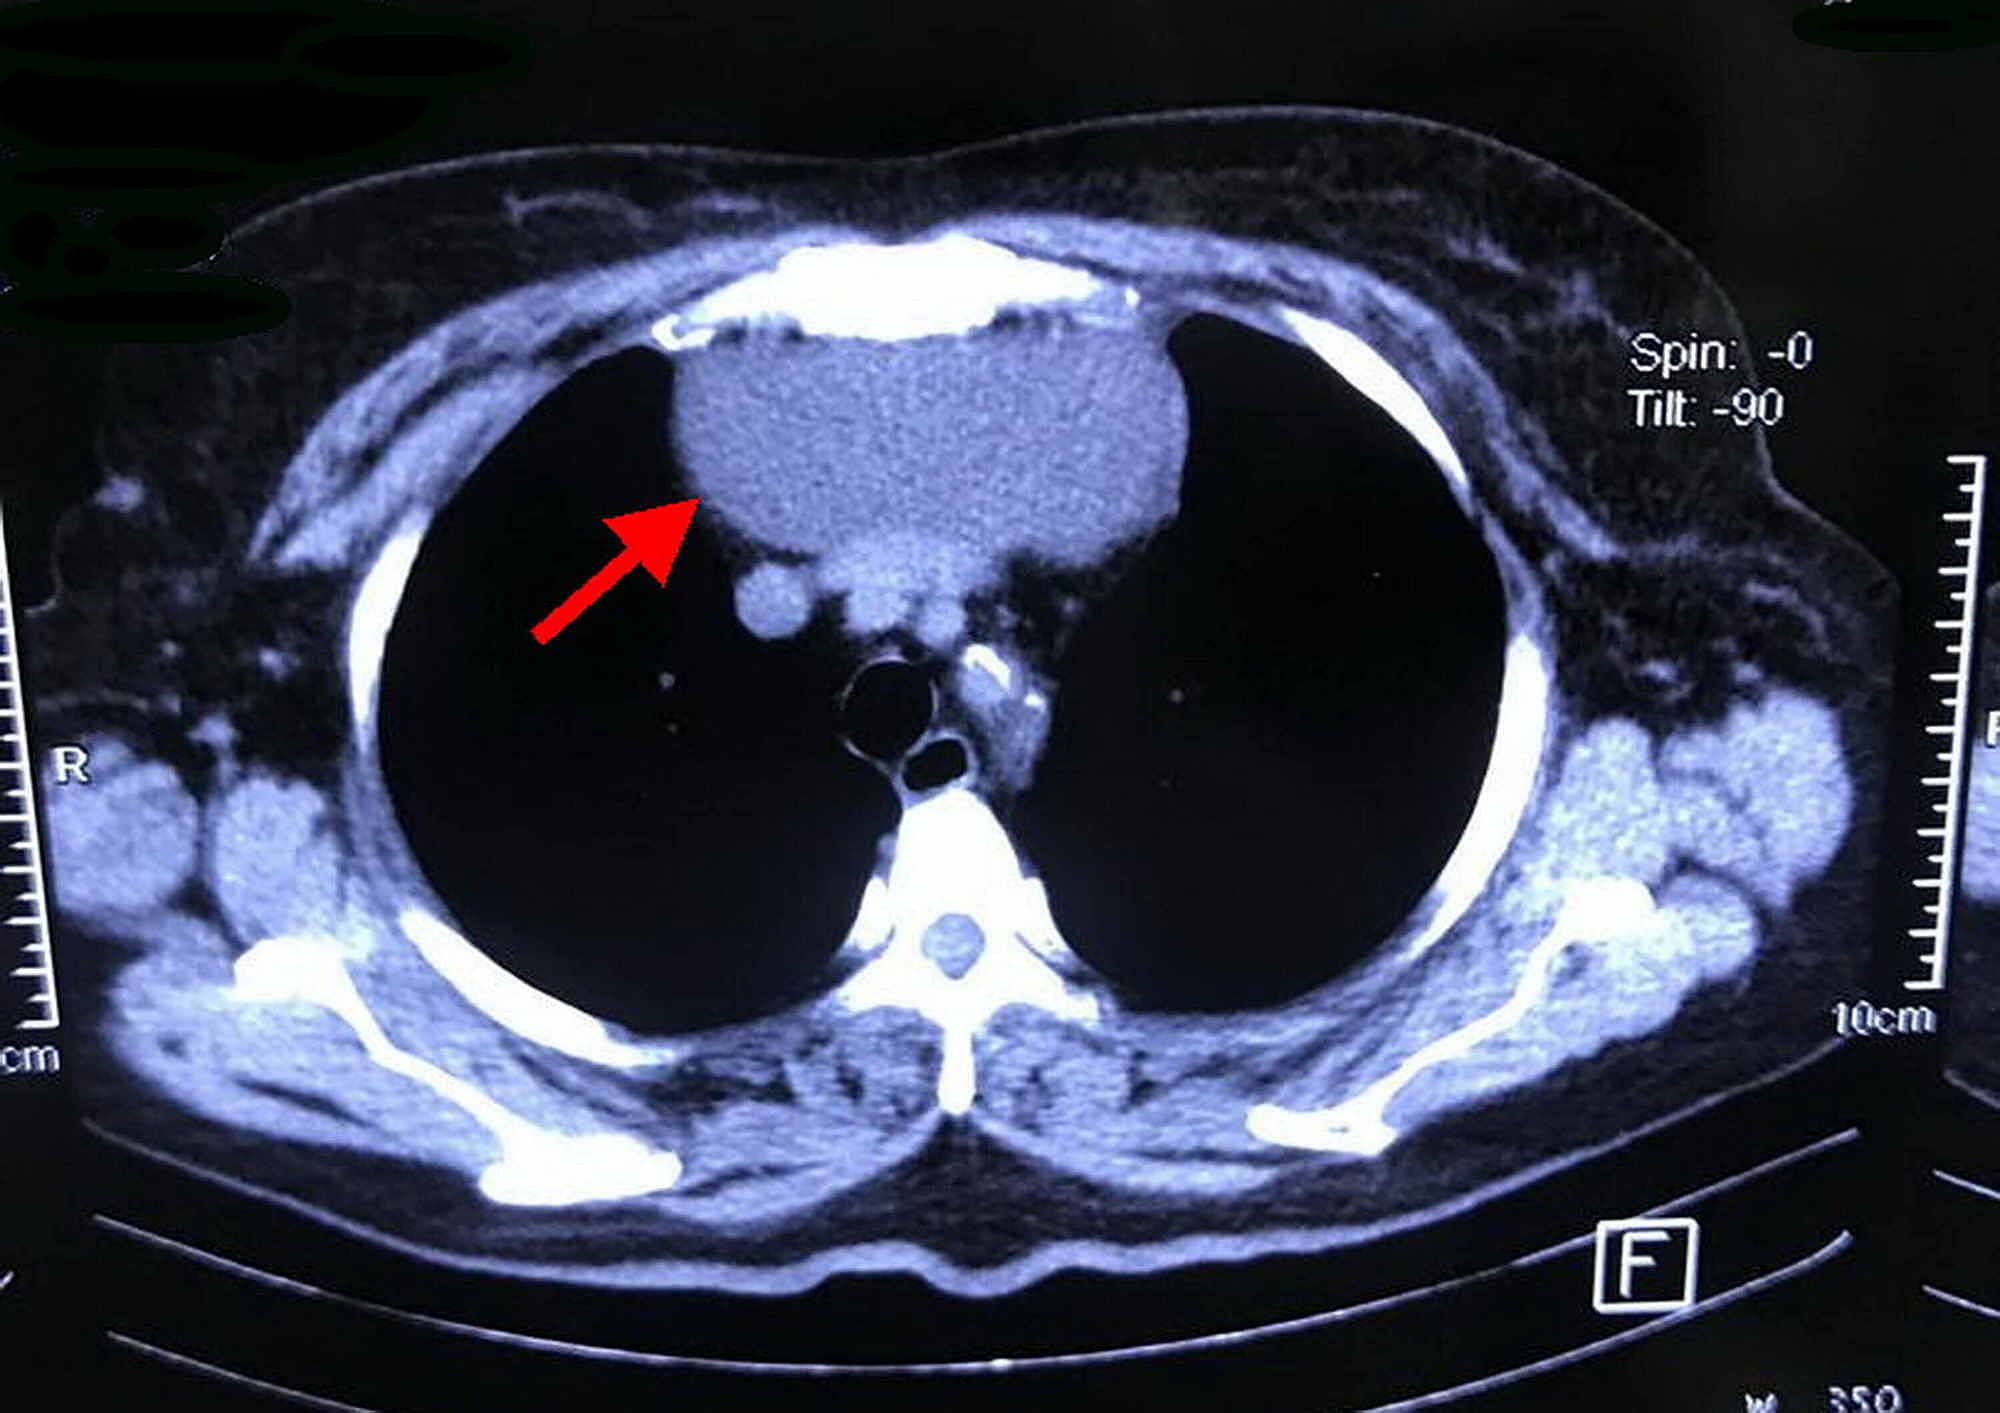

Cervical thymic cyst Image Thymic Cyst Neck Thymomas account for the vast majority of thymic neoplasms and are often associated with autoimmune. This study aims to discern different. a simple cyst has classically been defined as exhibiting a thin smooth wall with no mural nodularity or septations. the thymus is near the superior vena cava, the main blood vessel bringing blood from the head and. Thymic Cyst Neck.